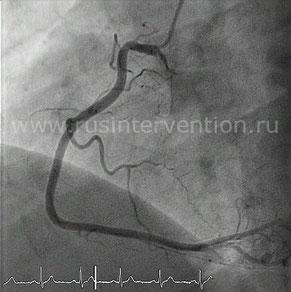

Ангиография левой коронарной артерии

Ангиография правой коронарной артерии

Коронарные артерии начинают отходить от аорты (синусов Вальсальвы) и делятся на левую и правую. Левая коронарная артерия далее распадается на две основные артерии: переднюю нисходящую и огибающую.

Передняя нисходящая артерия проходит по переднему межжелудочковому борозде и отдает крупные диагональные ветви, кровоснабжая переднюю стенку левого желудочка, передний отдел межжелудочковой перегородки, верхушку сердца и часть боковой стенки левого желудочка.

Огибающая артерия движется по левой предсердно-желудочковой борозде и также отдает ветви, кровоснабжающие заднюю и боковую стенки левого желудочка.